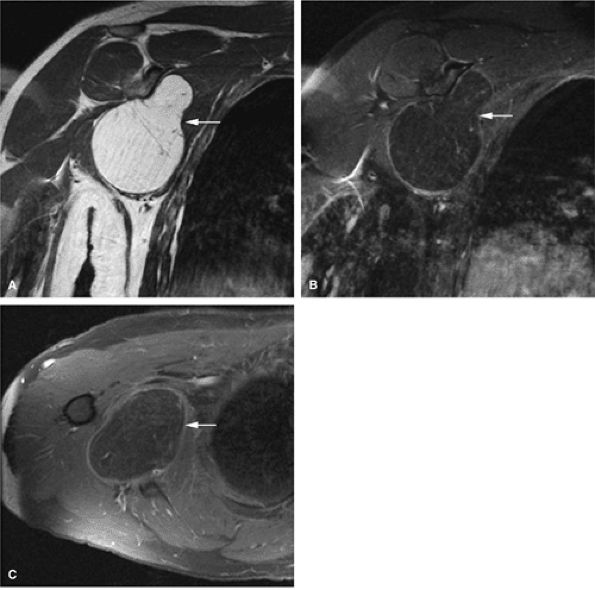

Low to intermediate signal intensity on T1-weighted images and high signal intensity on T2-weighted images (Fig. 14-64)92

Heterogeneity in T2-weighted images may represent central areas of liquefaction, hemorrhage, or necrosis (Fig. 14-65).

Aoki et al. reported MR detection of hemosiderin in 63% of giant cell tumors.93 The low-signal-intensity hemosiderin is attributed to extravasated erythrocytes in the tumor and the phagocytic function of the tumor cells. Areas of hemosiderin were most evident on gradient-echo sequences.

FIGURE 14-64 ● Giant cell tumor. (A) Anteroposterior and (B) lateral radiographs show an osteolytic lesion involving the subchondral bone of the tibial plateau. Cortical thinning and expansion can be seen. (C) Coronal T1-weighted image shows subchondral extension of the tumor (arrow). Tumor contents demonstrate low signal intensity on the coronal (C) and axial (D) T1-weighted images and are hyperintense on the coronal (E) and axial (F) T2-weighted images. Peritumoral edema (arrow) is noted on the axial fat-suppressed T2-weighted fast spin-echo image (F).